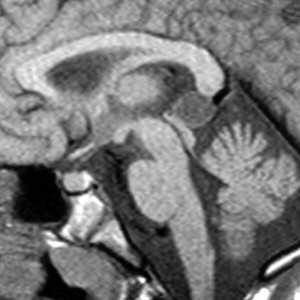

Дермоидные кисты встречаются реже эпидермоидных, составляя около 0,3 % от внутричерепных образований. Обычно выявляются в возрасте между 10 и 20 годами. Морфологически от эпидермоидов их отличает наличие эктодермальных элементов - волосяных фолликулов, потовых желёз и т.д. Типично они расположены по средней линии (в отличие от эпидермоидов, которые чаще внеосевые): в супраселлярной цистерне, субфронтально, вокруг моста и, очень редко парапинеально, периорбитально, в IV желудочке, в области конского хвоста и интрадиплоидно. От эпидермоидных кист на МРТ головного мозга их отличает только выраженная неоднородность структуры, кроме того, они всегда яркие на Т1-зависимых МРТ головного мозга за счёт большого содержания липидов. При разрыве и прорыве в субарахноидальное пространство в нём появляется уровень, на Т1-зависимых МРТ головного мозга светлый жир плавает на ликворе.

![Dermoid rupture]()

МРТ головного мозга. Т1-взвешенная аксиальная МРТ. Прорыв дермоидной кисты в субарахноидальное пространство.